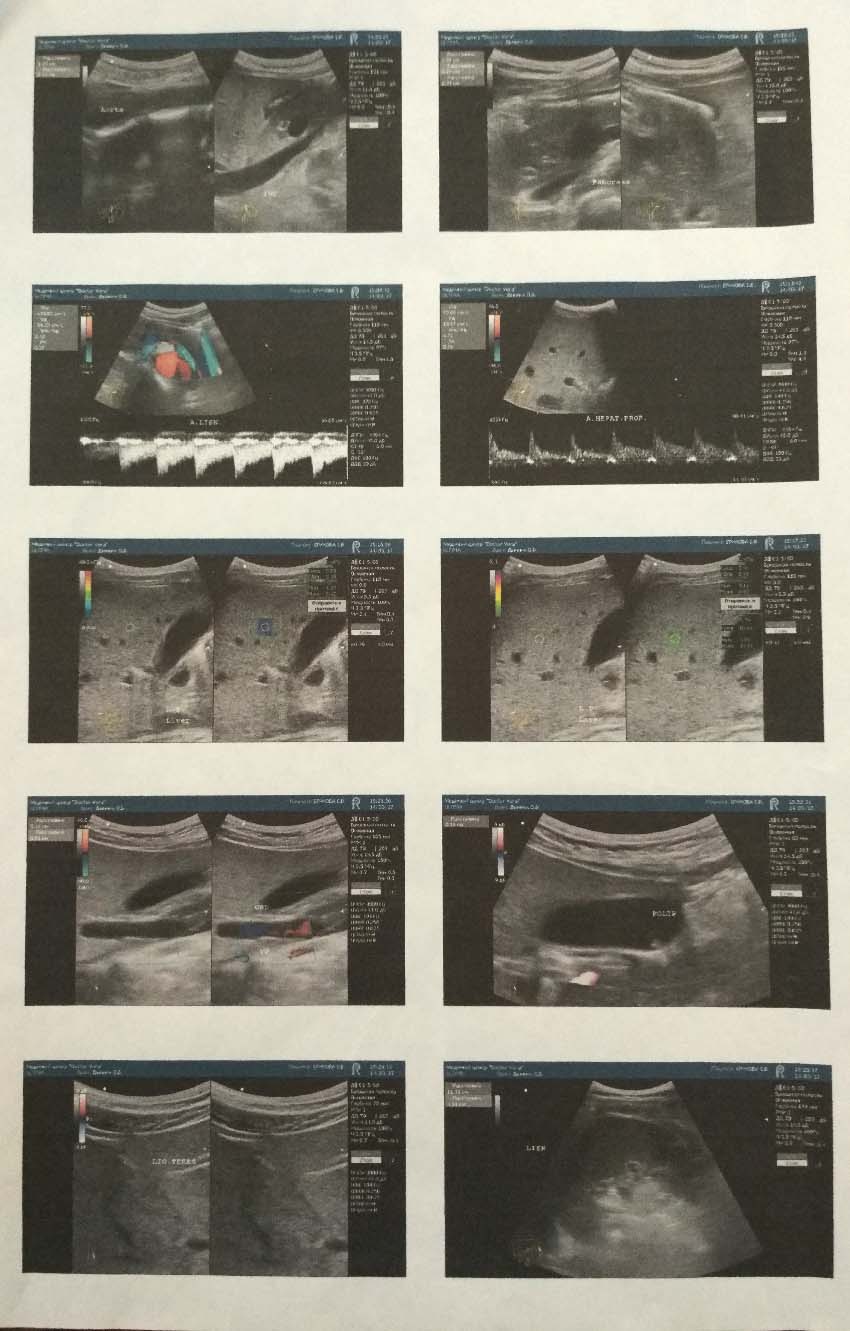

Потом был поиск хорошего врача и дополнительные исследования:

Не совсем ясно про кровотоки!

Норма в портальной 17-28 см/сек, в селезёночной <15см/сек. Мне док показывал нормативы общие!!!! Тут чет ваще дикие цифры стоят!!

Да вроде два опытных врача смотрели результаты УЗИ и никто не акцентировал на этом внимание. Да и доктор, который делал УЗИ и эластографию, считается светилом у нас, сказал что страшного ничего нет.Костян40 » 05 май 2017 02:34 писал(а):Не совсем ясно про кровотоки!